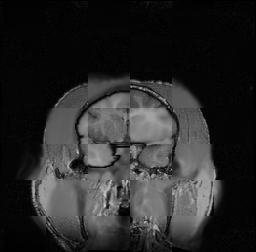

For each of the 10 subjects, we show checkerboard slices in each direction (1) before registration, first row; (2) after rigid->scaleversor->affine registration, second row; and (3) after BSpline registration, third row.

Calvin